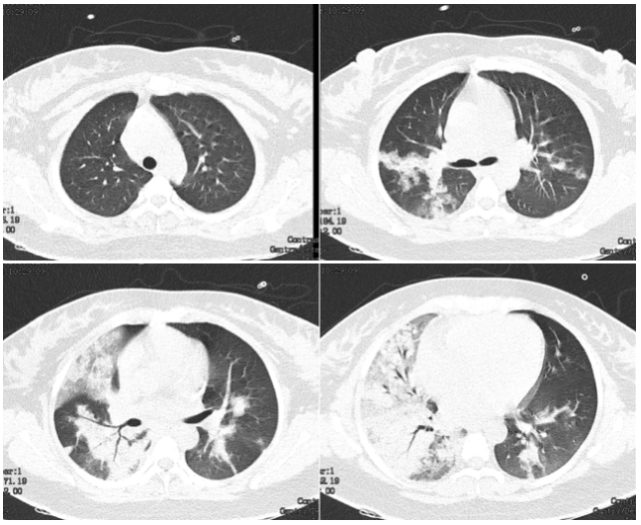

图 1 孕妇 26 岁,咳嗽发热 6 天,确诊 H1N1 流感病毒性肺炎